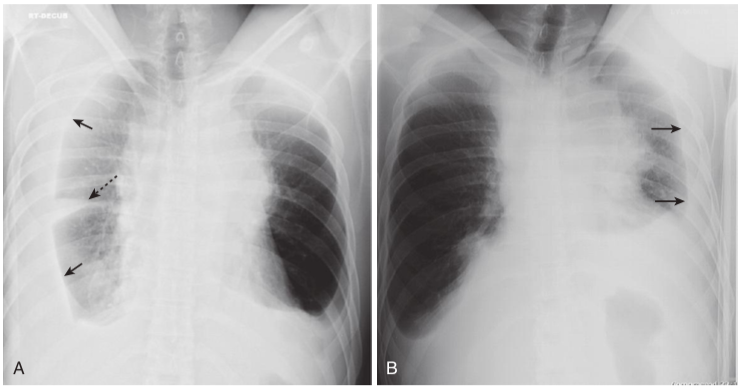

Decubitus views of the chest.

A, In a right lateral decubitus view of the chest, the film is exposed with the patient lying on the right side on the examining table while a horizontal x-ray beam is directed posteroanteriorly. Because the patient’s right side is dependent, any free-flowing pleural fluid will layer along the right side (solid black arrows), forming a bandlike density. Notice how the fluid flows into the minor fissure (dotted black arrow). B, In a left lateral decubitus view of the chest, the patient lies on the table with the left side down and free fluid on the left side layers along the left lateral chest wall (solid black arrows). Parts (A) and (B) show the same patient who has bilateral pleural effusions due to lymphoma.